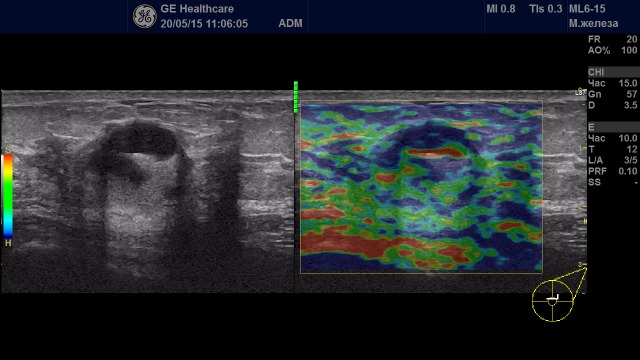

Образования с удовлетворительной эластичностью (тип I-III)